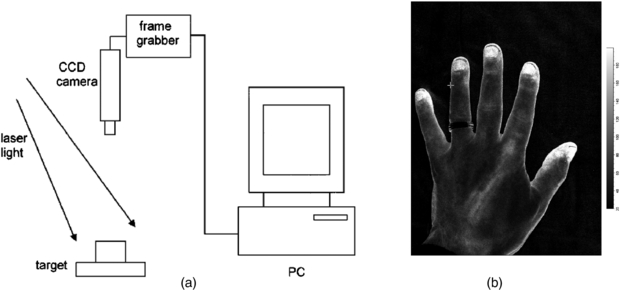

Standard image High-resolution imageRecent improvements in processing power mean that computational time no longer limits the imaging rate, since it is shorter than the data acquisition time. Image resolution is reduced by the necessity for averaging over a 5 × 5 pixel window, but resolution in practice is normally limited by photon scattering under the tissue (Boas and Dunn 2010). Figure 7 shows a schematic configuration of a laser speckle contrast imager.

Figure 7. (a) Schematic representation of a basic design of laser speckle contrast imager (reproduced with permission from Briers 2001 Physiol. Meas. 22 R35–66). In (b) an LSCI high spatial resolution image of the hand from a modern Moor Instruments FPLI-2 full field laser perfusion imaging system. The flux scale is also shown.